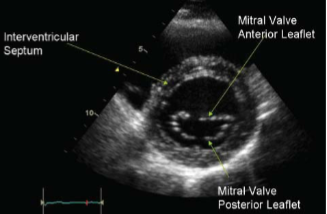

What ultrasound image is shown?

Parasternal short axis